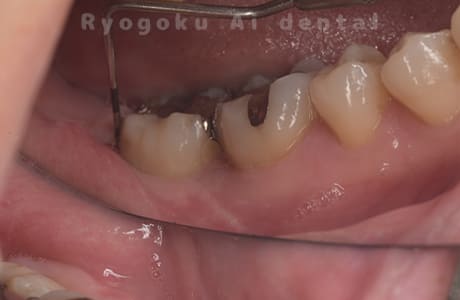

Case02

-

- 原因

- 重度慢性歯周病

- 治療内容

- 再生療法

- 治療費用

- 156,000円

左下からの出血がと違和感があるとのことで転院された患者さんです。衛生士さんとのブラッシング指導、並びに、歯石のお掃除を終えても歯周ポケットの改善がなかったため、再生療法を行いました。歯周ポケットが約8ミリ存在した部分が2ミリに改善し、出血もなくなりました。

<リスク・副作用>

手術後は痛み、腫れ、痺れなどの副作用が生じる場合があります。